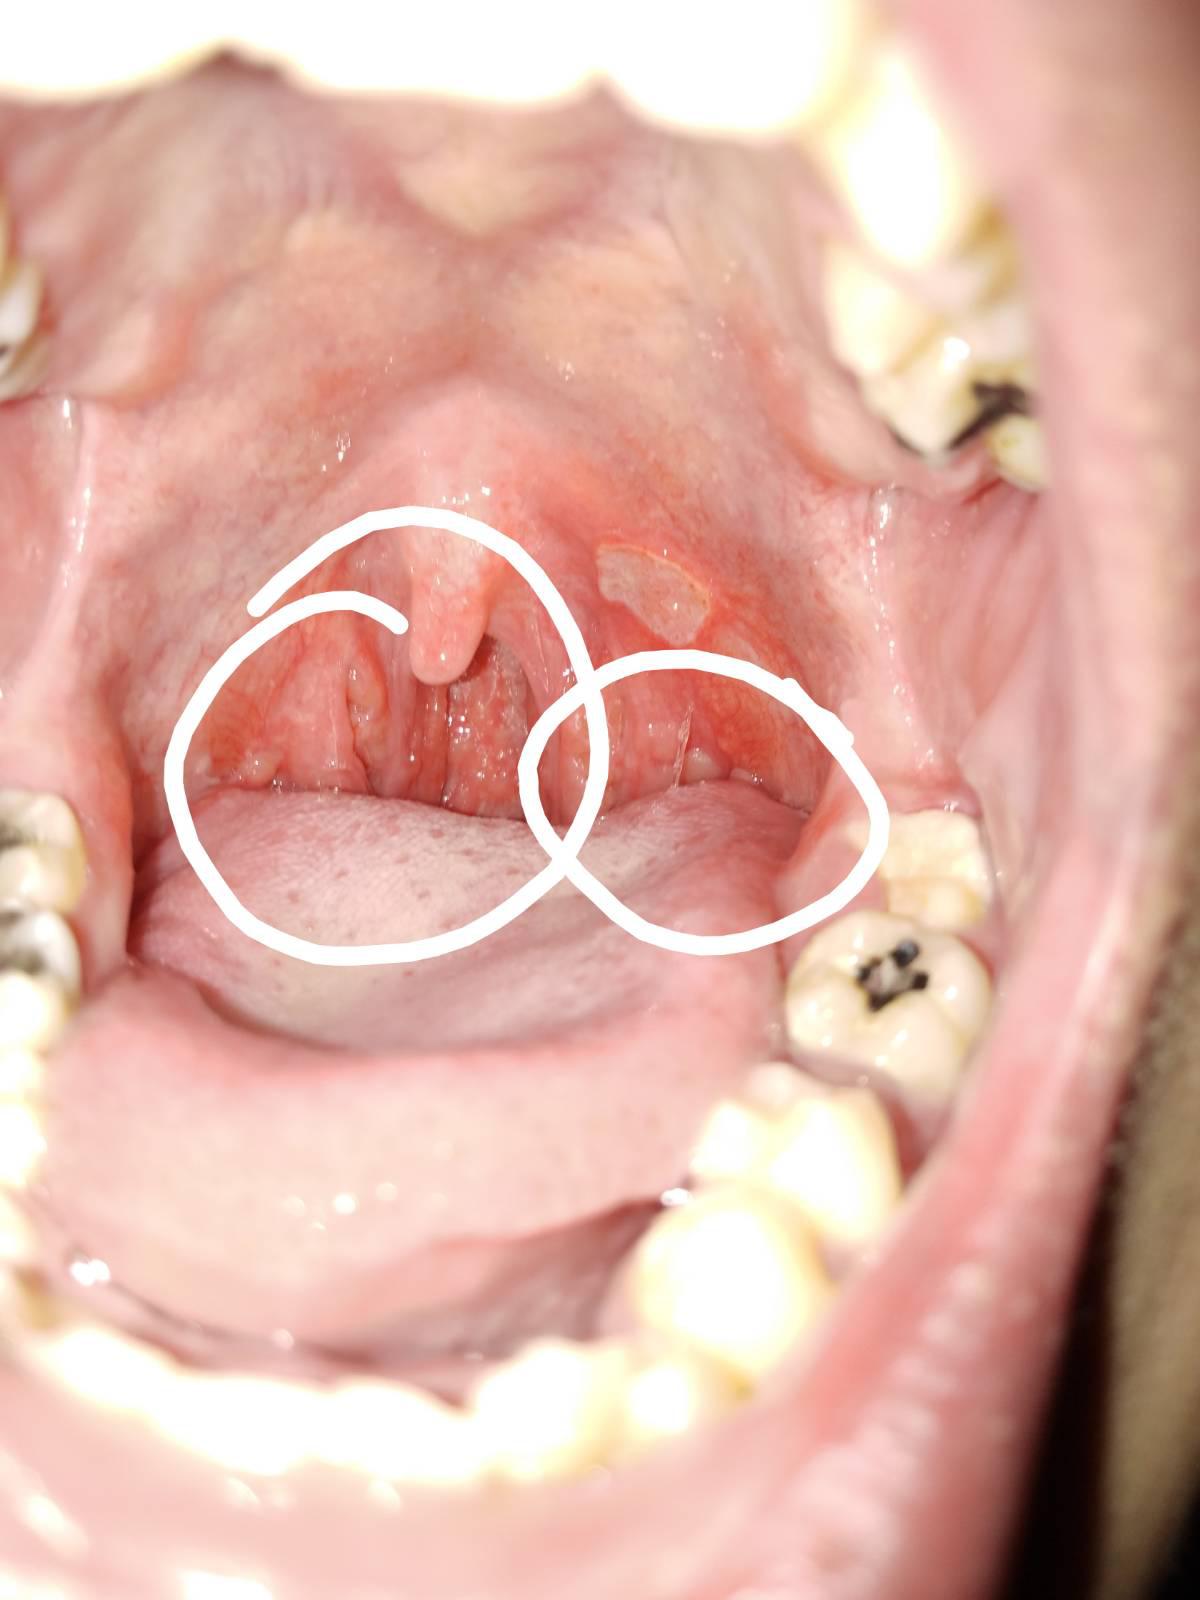

มีใครรู้บอกด้วยครับ ว่ามันเป็นอะไร??

คือเป็นมาสักเป็นปีล่ะมั้งเท่าที่สังเกต

แต่ร้อนในพึ่งเป็นได้จะอาทิตย์นึงล่ะคับ

ใครรู้ เป็นหมอมาตอบก็ได้ครับ กินยาแก้อักเสบไปครึ่งแผง แล้วครับ

เป็นมะเร็งรึป่าวครับ กังวลมาก

ขอผู้รู้มาตอบด้วยคับ ขอบคุณมากๆครับ